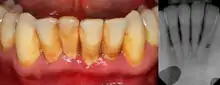

| Gingival enlargement can be a feature in some periodontal diseases. | |

Dental plaque is a microbial biofilm which forms on teeth. This biofilm may calcify and harden, termed calculus (tartar). Plaque tends to build up around the gingival margin (the gumline) and in gingival crevices or periodontal pocket (below the gumline). The release of waste products from the bacteria living in the biofilm causes an inflammatory response in the gums which become red and swollen, bleeding easily when disturbed. This is termed plaque-induced gingivitis and represents the most common form of gingival disease.[5] This inflammatory response in the host can be strongly influenced by many factors such as hormonal fluctuations, drugs, systemic diseases, and malnutrition;[4] which may allow further subdivision of plaque-induced gingivitis (see table).

Periodontitis

The defining feature of periodontitis is connective tissue attachment loss which may manifest as deepening of periodontal pockets, gingival recession, or both. This loss of support for the teeth is essentially irreversible damage. Chronic periodontitis is generally slow to moderate in terms of disease progression, although short bursts of increased tissue destruction may occur. Ultimately, tooth loss may occur if the condition is not halted. It is termed localized when less than 30% of sites around teeth are involved, and generalised when more than 30% are involved. clinical attachment loss can be used to determine the severity of the condition, where 1–2mm is slight, 3–4mm is moderate and more than 5mm is severe.[5]